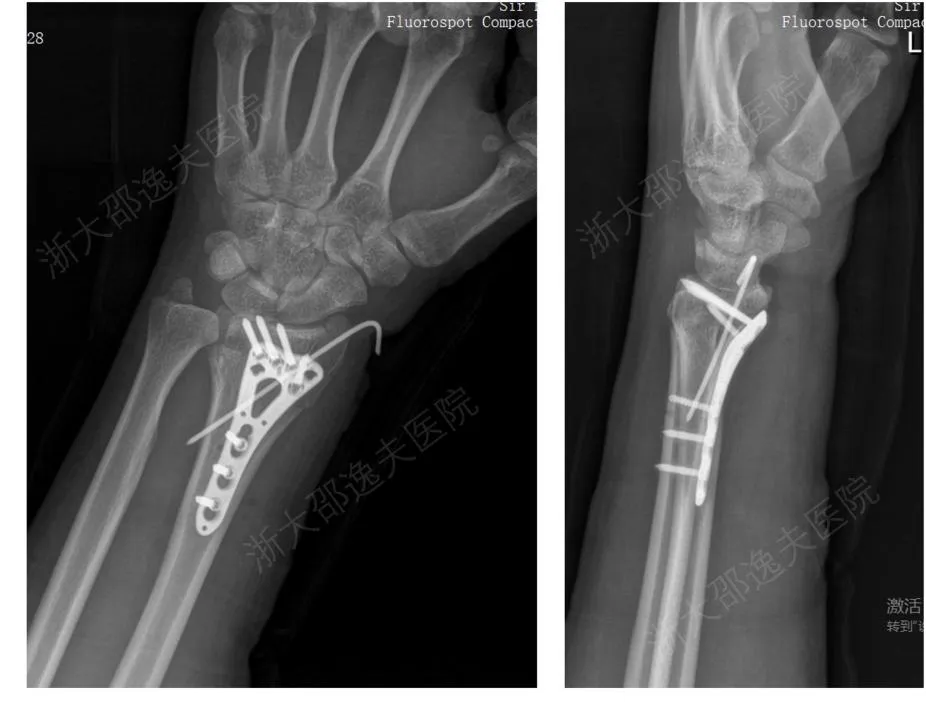

一位年轻工人因外伤导致腕部桡骨远端粉碎性骨折,传统治疗方案需大切口植入钢板螺钉,不仅创伤大、存在肌腱粘连或神经损伤风险,且需术后一年行二次手术取出。

应用“骨02”黏合技术,仅通过微创切口注入“胶水”材料,短短3分钟内即完成了粉碎骨块的精准黏合与固定。术后3个月随访显示,患者骨折愈合良好,无并发症,腕关节功能完全恢复。